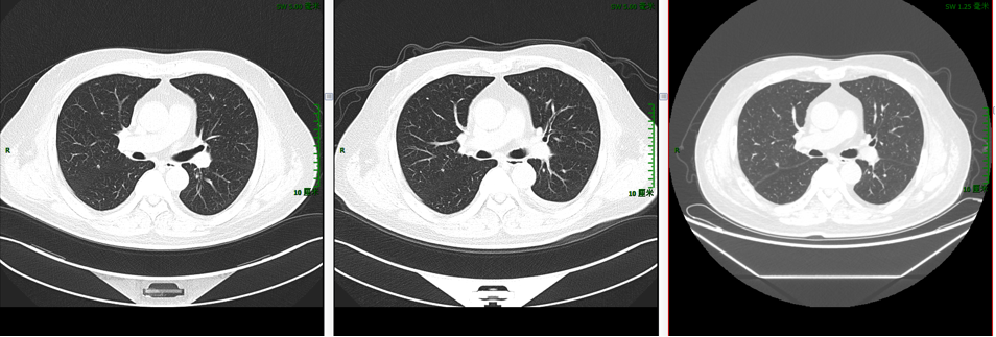

【贝伐珠单抗+雷替曲塞+奥沙利铂】2020-2-11 上腹部MRI增强:“直肠CA根治术+肝转移瘤切除术+胆囊切除术”后改变,与前片(2019-5-9)相仿,肝右叶局部强化欠均,但未见明确的占位性病变。

2020-3-6 胸部CT:两肺多发小斑点灶及微小结节,直径约3-10mm,较前(2019-11-05)部分增大。评估病情PD。